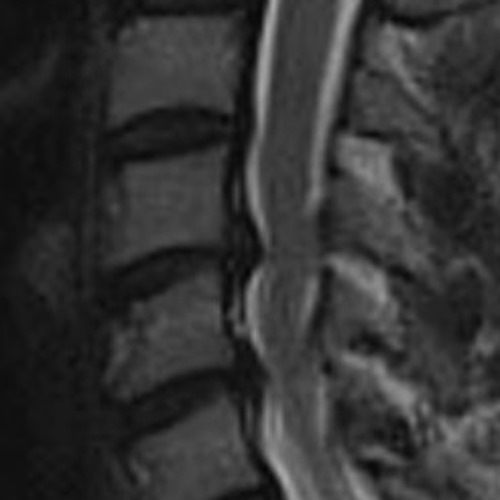

09112023

Von oben/vorne ran, Bandscheiben raus, beim Kreis fräsen (das ist die Nervenwurzel, die gerade bedrängt wird), das Viereck – den Cage – einsetzen und im Bild links hat sie eingezeichnet, wo das ganze theoretisch verschraubt werden soll. Je nach Knochenqualität evtl. auch mit einsetzen einer Metallplatte.

09112023II